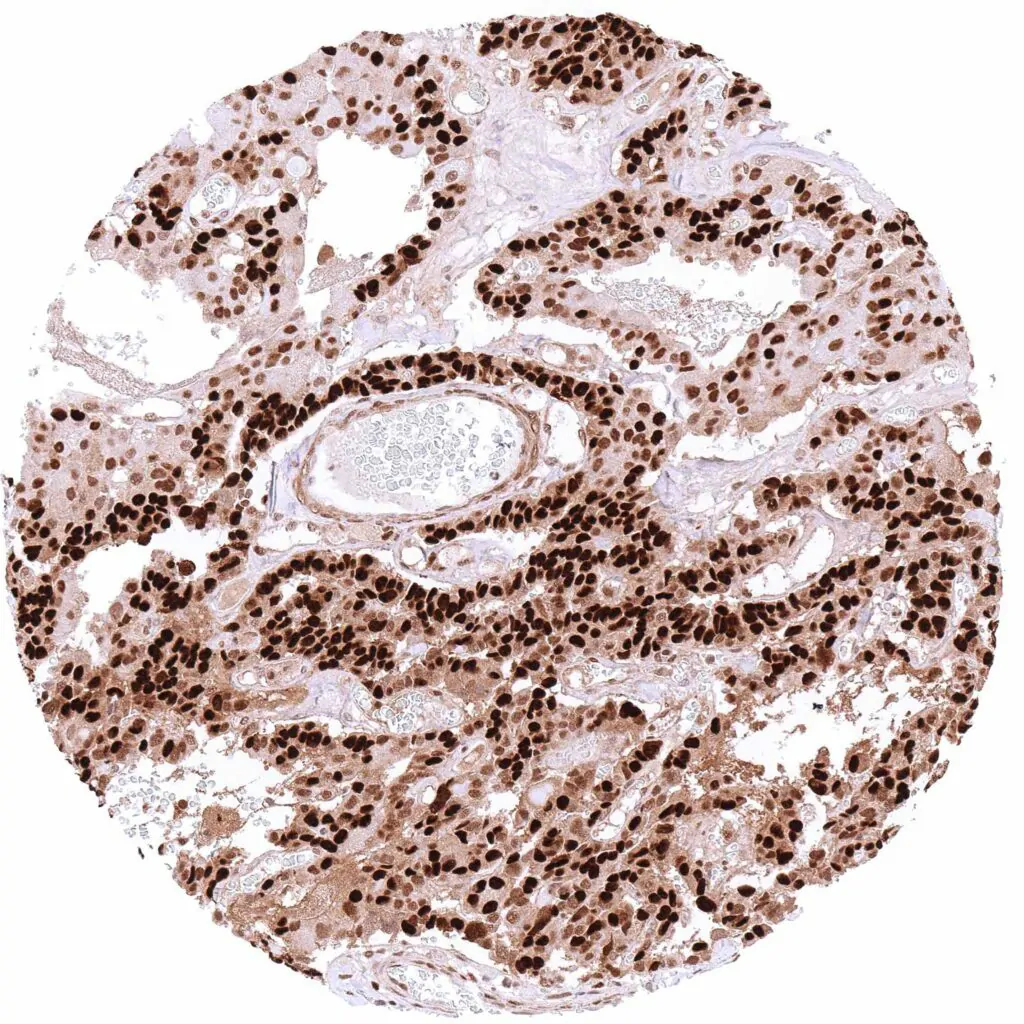

p27 Kip1 antibody [HMV3970] HistoMAX™

Lymph node – B-CLL with intense nuclear and cytoplasmic p27 positivity of all tumor cells.